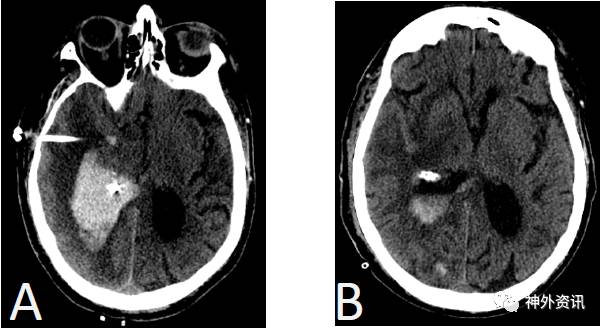

76岁男性患者,以精神状态改变和左侧肢体无力收治入院。头颅CT平扫显示右侧基底节区脑出血,血肿量达48ml,伴周围水肿和脑室内积血(图1)。术前将头颅CT扫描资料上传至ROSA系统,确定安全的穿刺轨迹与目标区域。患者全麻后,取仰卧位,头向左转45°。在ROSA系统帮助下,确定皮肤切口;颅骨钻孔后利用ROSA系统的peel-away鞘通过钻孔沿已定方向穿刺,按预先明确的深度达血肿腔。随后,置入引流管到血肿腔内进行引流(图2)。接着,采用同样方式将脑室外引流管放入右侧侧脑室颞角(图3)。术后头颅CT显示置管满意,颞角缩小。在术后48h内,通过导管向血肿腔注射2mg阿普替酶。经多次头颅CT扫描显示,血肿量逐渐减少到14.7ml、10.1ml,最终小于1ml。术后第三天将两根引流管拔除。

图3. 术后基底节区血肿吸收,颞角缩小。A.术后立即行CT平扫证实引流管置入脑内血肿,位置准确;另外一根引流管置于颞角,获得满意的减压效果;B.48小时后,CT平扫证实血肿明显吸收。